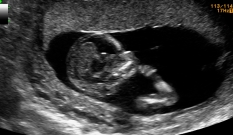

O ultrassom do primeiro trimestre Embora possa ser feito um pouco antes ou um pouco depois, hoje em dia, o momento mais comum para fazer um ultrassom de primeiro trimestre é quando se completam 12 semanas. Isso porque, neste momento, o desenvolvimento anatômico e o tamanho do feto permitem comprovar que a maioria dos órgãos se formaram adequadamente.

Um ultrassom de alto nível neste momento pode detectar até 60-70% dos possíveis problemas de malformação que aparecerão na gestação. A outra medição que se faz é a da translucência nucal, o líquido que todos os fetos têm na nuca.

A espessura da nuca do feto é medida e seu valor é utilizado como parte do rastreamento genético do primeiro trimestre. Como já comentamos, esse conjunto de exames permite estimar o risco de uma anomalia no número de cromossomos (tecnicamente definida como aneuploidias), especialmente a trissomia do cromossomo 21 (síndrome de Down). Para o cálculo do risco, o valor da translucência nucal é combinado com a idade materna e os valores de dois hormônios (beta-hCG e PAPP-A), identificados em análise do exame de sangue.

Também é possível usar a informação desse ultrassom do primeiro trimestre para incluir no rastreamento do primeiro trimestre o cálculo do risco de pré-eclampsia.